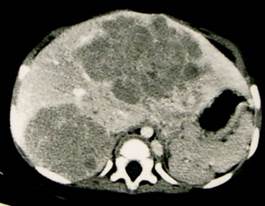

图1 位于肝右的叶肝母细胞瘤, 6个月,男婴

1)平扫:可见肝实性肿块,多由数个结节聚合成大块状,其边缘为高或等密度,中心呈低密度或高低不等密度。

2)增强扫描:在动脉期增强可见多个结节状增强染色征象,门静脉期肿瘤呈低密度,中心有不规则更低密度区域,为肿瘤坏死所致。有的肿瘤内含类似骨组织成分,CT 可显示钙化灶。CT平扫示右肝可见巨块状低密度占位性病变,边缘比较光滑,密度不均,内部可见不规则更低密度区域,其内斑点状钙化。增强示肿瘤可见增强,门静脉期肿瘤呈低密度,中心坏死无增强,肝内胆管扩张。

图2:肝右叶肝母细胞瘤的CT表现, 6个月男婴